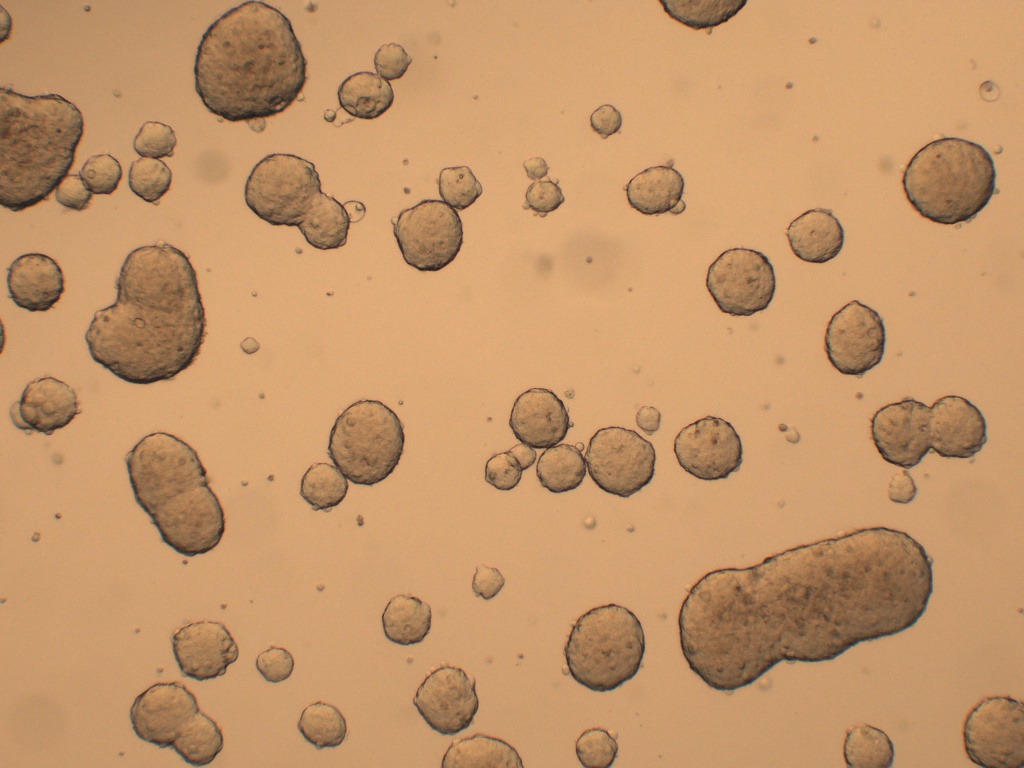

Cancer Stem cells Spheres Medium(肿瘤干细胞成球培养基)是一款用于将癌症干细胞(CSC)培养成3D球的培养基���。癌症干细胞(CSC)被定义为肿瘤内的一小部分细胞���,具有自我更新的能力����,并且经常在化学疗法治疗后驱动肿瘤的进展和复发����。因此����,针对CSC的特定疗法的开发有望改善癌症患者的生存和生活质量���,特别是对于患有转移性疾病的患者�����。

肿瘤干细胞成球培养基是一种新的化学成分确定和无血清的癌症干细胞培养基�����,可支持CSC形成3D球状细胞的聚集和扩增�����。

6、 根据使用的细胞类型����,孵育培养物 4-10 天。每 3-4 天半换一次新鲜肿瘤干细胞成球培养基�����。不要像传统二维细胞培养一样一次性更换所有培养基;

7、 4-10 天左右在超低吸附板孔中央区域会形成肿瘤球体;